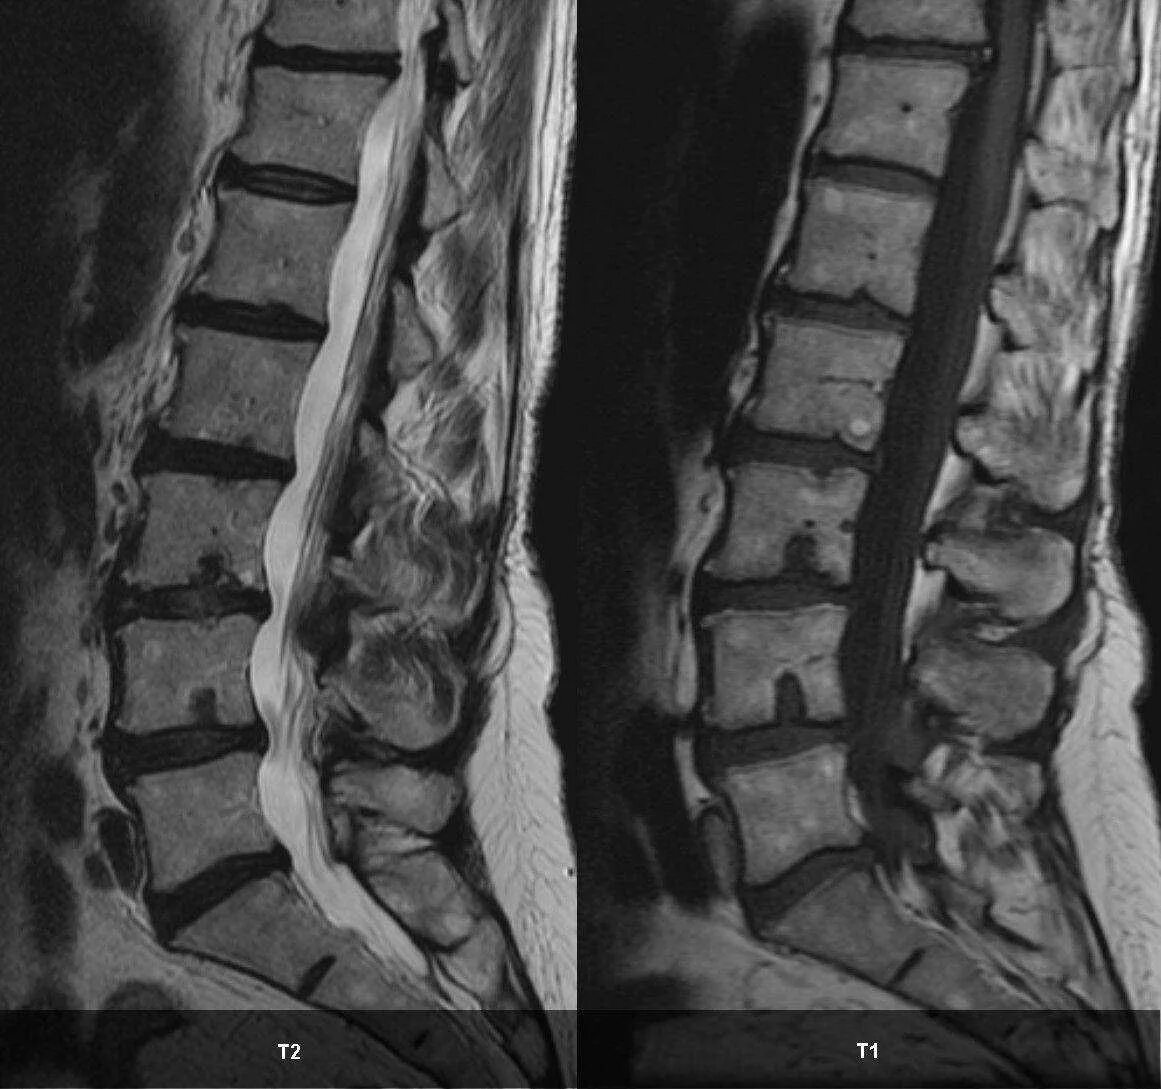

Протрузии шморля